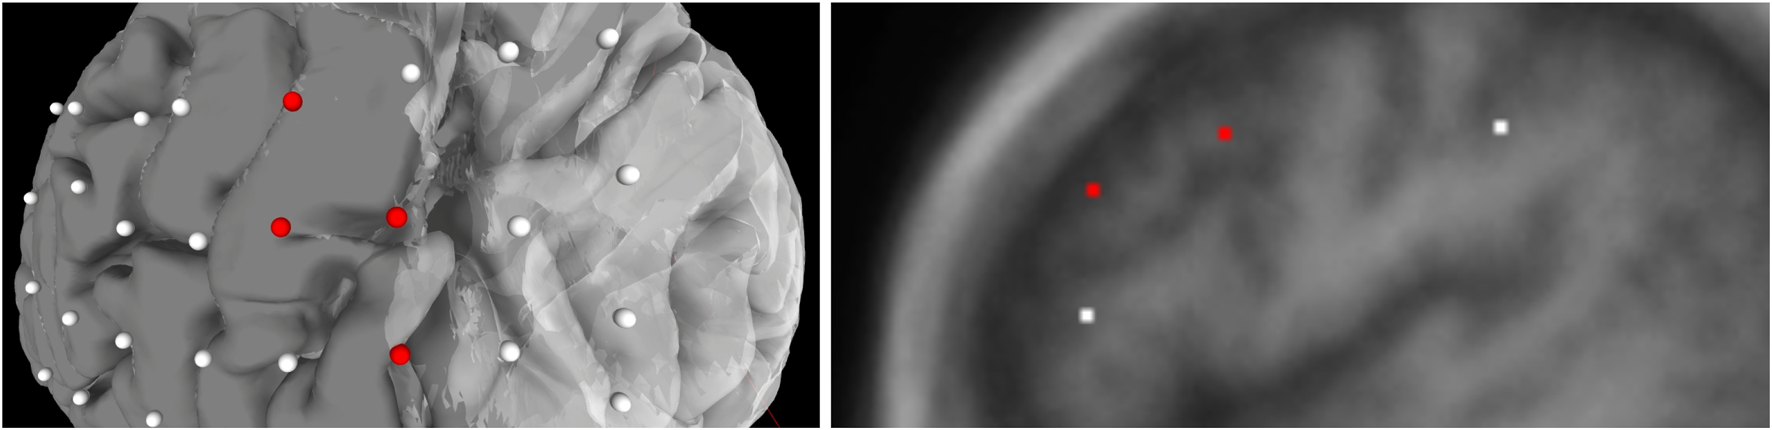

The JSON file also contains an array for each seizure type of a particular subject. Each type of seizure activity is mapped onto a specific color, and a legend showing this mapping is displayed in the UI. Figure 3 provides an example of this legend for a particular seizure type, and Figure 4 shows electrodes of type “onset” mapped to a brain surface after loading.

Population of electrodes on the brain in 3D space (left) and on a 2D slice (right) in the x-direction. The red electrodes represent the “onset” attributes of associated seizure type, while white indicates no seizure type is associated to the electrode.

We added WebGL’s dat. GUI for direct visibility and to enable interactive manipulation for the user. We separate the electrode and functional map data from the slice and mesh controllers by using two panels. Figure 4 shows the one panel in two segments responsible for controlling the slices and hemisphere meshes. Users can use this panel to select a specific slice number, control the opacity of the slices and hemisphere, and toggle visibility of the slices. This makes it easier to find needed information more quickly.